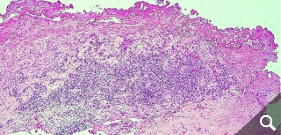

Skin tests (epicutaneous tests) do not show a clear correlation to the reaction of a joint to the implant, so that even skin testing for a metal or cement allergy cannot give a 100% indication. Therefore, in case of doubt, it is necessary to perform a tissue biopsy from the affected joint to provide the appropriate level of certainty. In the case of an allergy, lymphocyte infiltrates are frequently found in these tissues.